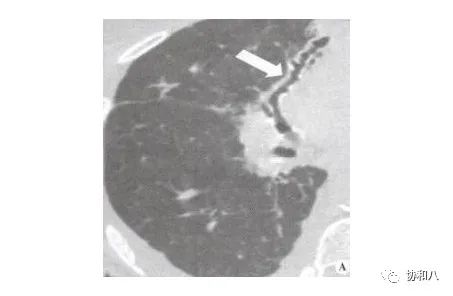

4. 葡萄串征:

常用于描述囊状支气管扩张(图1&2)的典型CT表现,也见于结肠含气囊肿(图3)。描述:簇状/串状囊腔呈葡萄串样。

左滑高能预警